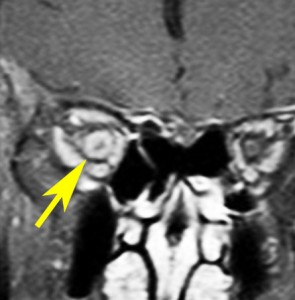

視神経鞘髄膜腫 optic sheath meningioma

眼窩内腫瘍です。視神経を包むし神経鞘から発生して,視神経鞘に沿って進展して増大します。視神経を圧迫してゆっくり症状が出ます。片目の視力が落ちるというのが症状ですが気づかれず発見が遅れることが多いでしょう。眼底検査で,初期には視神経乳頭 optic discの腫れが見られ,視力が悪化していくと視神経萎縮となります。眼底検査で動静脈シャントが見られるのも特徴的で,視力低下と視神経萎縮と併せてHoyt-Spencer triadと言われました。視力がほぼ消失するまで腫瘍が増大すると,眼球が前に押されて,眼球突出 exophhalmus, enophthalmus という症状が出ます。

治療は手術摘出ですが,この腫瘍を摘出するとほぼ確実に片眼の視力を消失します。ですから視力が無くなるまで手術は待機するという考え方が一般的です。数年以上視力があまり低下しないで腫瘍も増大せず経過する患者さんもいます。視力温存目的で治療するなら,視力の良いうちに定位放射線治療を行うべき疾患です。だからといって何でも定位放射線治療をすればよいというものではありません。問題は,視神経管から鞍結節に腫瘍が伸展している例があるということです。ここを放置すると反対側の健常な眼の視力が侵されることになりかねないので慎重に判断します。

比較的急速に視力低下して手術摘出した例

右目が暗いという症状で発症して,眼科では視神経乳頭腫脹とわずかな視野欠損だけで発症した患者さんです。3年間観察されましたが,その間には眼底所見も視力 Vd 1.2 も変化がなかったとの眼科からの報告です。そのすぐ後で患者さん本人は,右目が暗くなる回数が増え、視野狭窄があり軽い眼球突出,まわりがぼやけてますが中心は1.0見える状態との訴えで相談を受けました。主治医の先生の方針では経過観察ということで,まだ視力も良いので私もそうした方がよいと同意したのですが,その後半年くらいで視力が手動弁まで低下してしまいました。眼球運動と右眼球を温存するために腫瘍を摘出しました。

左側は,摘出標本の輪切りの写真です。この部位は腫瘍の発生した部位ではありません。一番外側にみえるのは視神経鞘 optic sheathという膜です。その内側が髄膜腫で,その内側が視神経です。すなわち髄膜腫は,視神経鞘と視神経の間のくも膜下腔を,這うように伝わって増殖伸展しています。このくも膜下腔には視神経への栄養動脈や網膜動脈も入っているので,この腫瘍だけを視神経や細動脈を傷つけずに摘出することはできないのです。